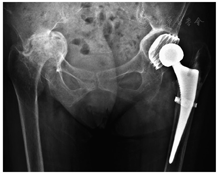

入院后第3天,在腰麻下行左侧全髋关节置换术。患者侧卧位,经改良Hardinge入路逐层切开皮肤、皮下组织及阔筋膜,紧贴臀中肌大转子处附着点,部分切断臀中肌、臀小肌,经股直肌与臀中肌、臀小肌间隙显露关节囊。切除关节囊并处理周围软组织,显露骨折线。用取头器取股骨头,未能顺利取出。经检查见髋臼周缘增生明显致髋臼口狭窄,髋臼口呈握拳状包绕股骨头。换用小号髋臼锉缓慢对股骨头进行磨除,剩余约1/3股骨头时成功将其取出。探查髋臼形态,见髋臼呈"葫芦状"(口小腔大),且髋臼马蹄窝被增生的骨质填充。使用电刀清除软组织,用咬骨钳清除增生骨质,找到真正的髋臼底皮质骨,打磨髋臼。当磨锉至49号时,髋臼锉边缘与髋臼周缘恰好贴合。但由于髋臼腔大口小,髋臼锉未达髋臼底部,无法使用生物性臼杯通过压配的原理进行固定。于外展45°、前倾15°位拧入49号BICON-PLUS螺旋臼(施乐辉,瑞士),检查臼杯稳定性并关窗,置入32号聚乙烯内衬。屈髋并内收、外旋股骨,暴露股骨近端,继续处理股骨侧。使用股骨柄锉扩髓至3号时,股骨矩处骨质出现劈裂,采用捆绑带固定。放置3号股骨柄试模,锥度位于髋臼上缘约5 cm处,复位困难。改用0号股骨柄假体(Polarstem,施乐辉,瑞士),打入骨水泥固定。骨水泥凝固后安装32+0号黑晶球头(施乐辉,瑞士),复位髋关节。检查关节活动度,屈髋、内收、外展、外旋均无脱位。术后摄髋关节正位X线片,观察假体位置(图3)。